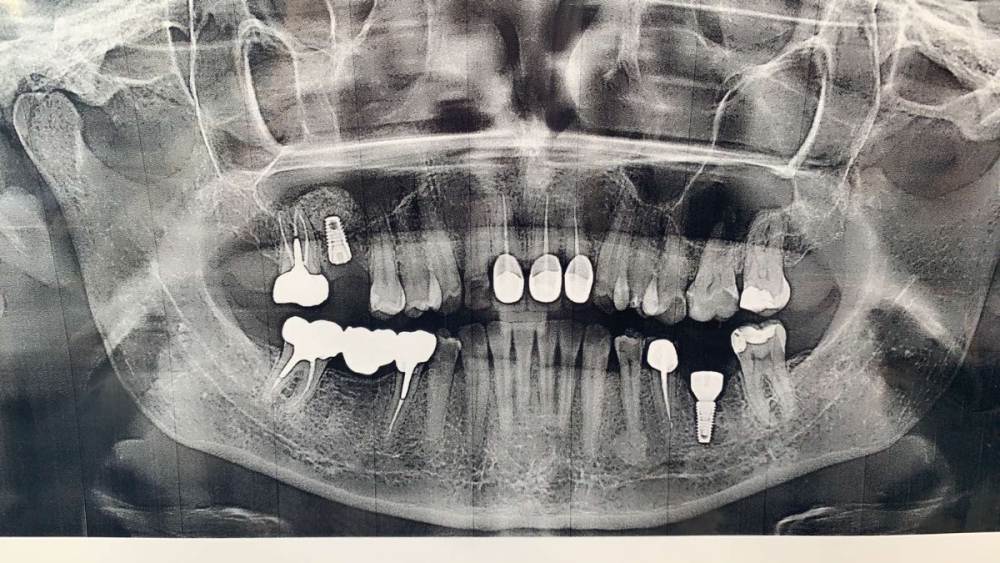

Kalipso2101 Опубликовано 2 октября, 2021 Автор Поделиться Опубликовано 2 октября, 2021 51 минуту назад, сирена сказал: Уплотнение кости - не патология.С удалением нерва я бы подождала.А ОПТГ свежая или сразу после имплантации? Сегодня делала снимок этот. С имплантами что то не так ? Ссылка на комментарий

сирена Опубликовано 3 октября, 2021 Поделиться Опубликовано 3 октября, 2021 Да нет,по снимку не скажешь,что с имплантом что-то не так,но клинические симптомы(боль,отёк) говорят,что да,что-то не так.Мы Вам больше не скажем,потому-что нужен очный осмотр и кт бы посмотреть. Ссылка на комментарий